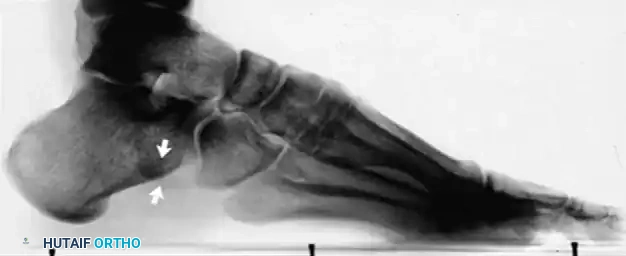

Figure 82-47: (A) A 61-year-old man with a rupture of the peroneus longus tendon and a varus right foot. (B) Note the hypertrophic os peroneum and its proximal migration following the rupture.

- Plain Radiographs: Essential for identifying bone avulsions (e.g., "fleck sign" of the superior peroneal retinaculum) or the proximal migration/fracture of an os peroneum.

Figure 82-48: (A and B) Radiographs demonstrating a tear of the peroneus longus with proximal retraction of the sesamoid bone (os peroneum). (C) T2-weighted MRI showing a type I tear of both the peroneus longus and peroneus brevis tendons.